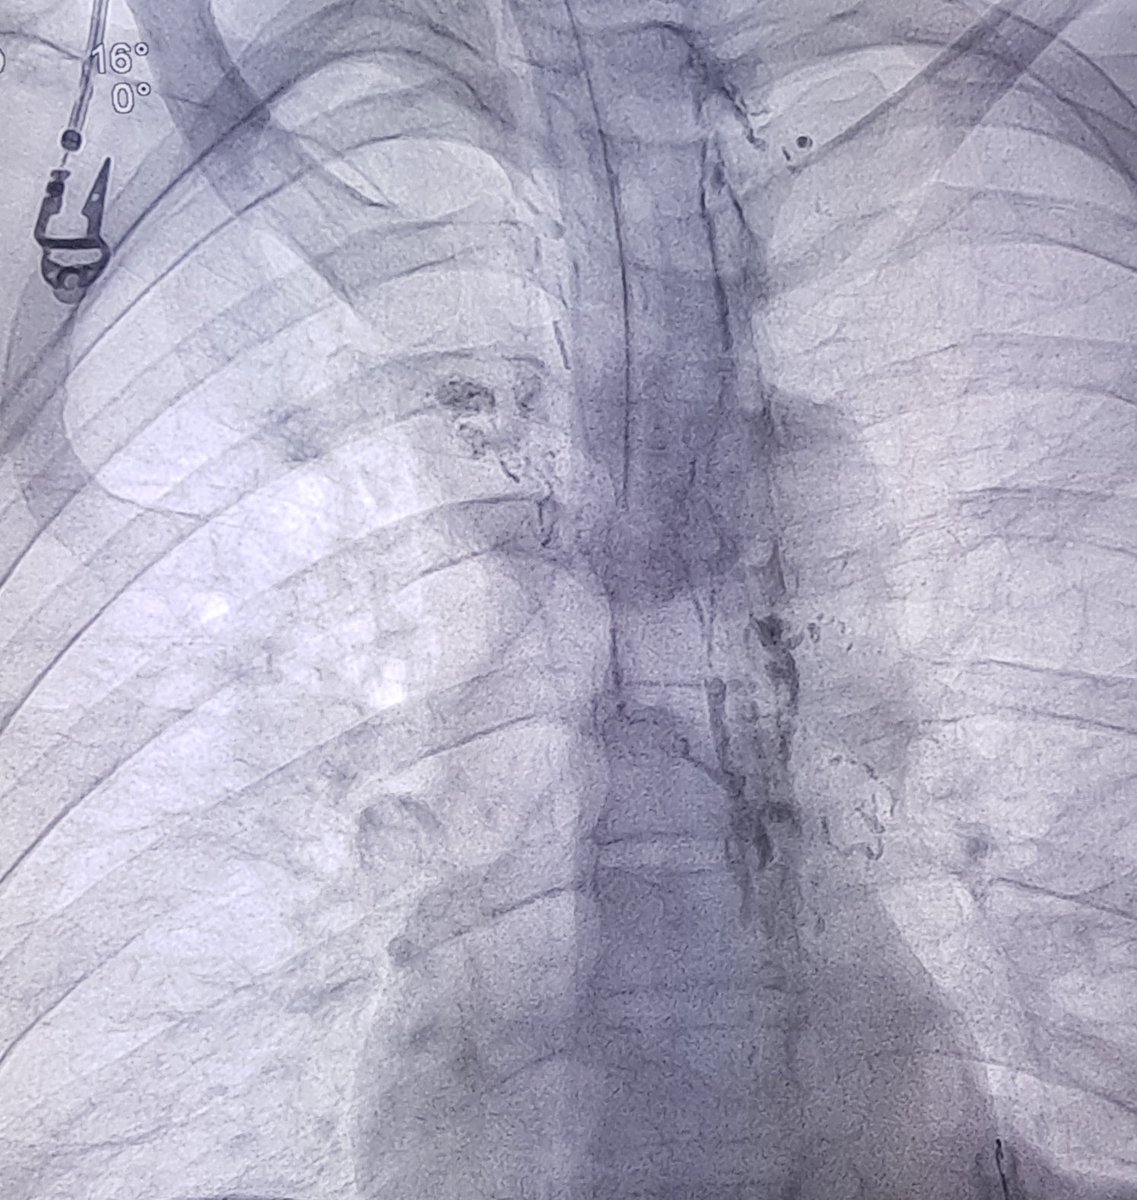

Abdominal pain and bloating caused by occlusion of the Thoracic Duct. Dilation of the Thoracic duct-Venous junction with balloon and removal of the debris from Thoracic Duct result in complete resolution of the symptoms.@SIRspecialists @PennRadiology #lymphatics #abdominalpain